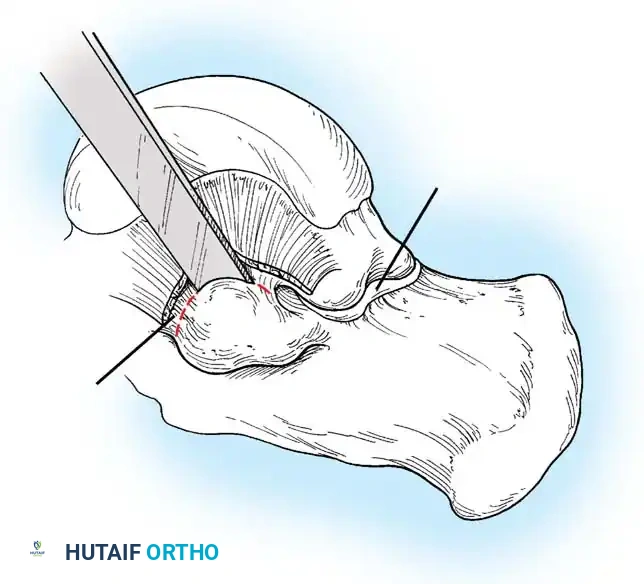

2. Transposition and Advancement of the PTT

-

Ossicle Excision: Using sharp dissection, meticulously shell the accessory navicular out from the substance of the posterior tibial tendon. If transposition of the tendon is planned, attempt to leave a microscopic sliver of bone within the tendon to enhance subsequent bone-to-tendon healing.

-

Navicular Resection: Resect the medial prominence of the main navicular so that it is flush with the medial border of the first cuneiform. This is typically achieved using an osteotome, followed by a rongeur and rasp to smooth the cortical edges.

-

Tendon Advancement: Suture the PTT to the apex of the medial longitudinal arch. This can be achieved by utilizing local periosteum and ligamentous tissue to secure the transposed tendon slip, or by passing heavy non-absorbable sutures through drill holes placed in the center of the navicular and tying them dorsally.

- Biomechanical Reduction: Try to advance this slip of tendon while the talonavicular joint is anatomically reduced. Reestablish the medial longitudinal arch by holding the midfoot and forefoot in a cavovarus position during knot tying.